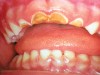

Figure 4  Classic early childhood caries demonstrating massive destruction of maxillary anterior teeth.

Figure 4